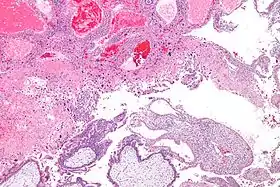

ينبغي تأكيد التشخيص السريري الأولي بمرض ورم الأرومة الغاذية الحملي تشريحيا، والذي يمكن القيام به بعد اخلاء الحمل (انظر «العلاج» أدناه) لدى النساء المصابات بحمل الرحى العدارية الجزئي.[18] ومع ذلك، مرض ورم الأرومة الغاذية الحملي الخبيث وعائي للغاية. في حالة الاشتباه بوجود مرض ورم الأرومة الغاذية الحملي الخبيث سريريا، فهذا يعتبر من موانع اجراء الخزعة، لأن الخزعة قد تسبب النزف المهدد للحياة.